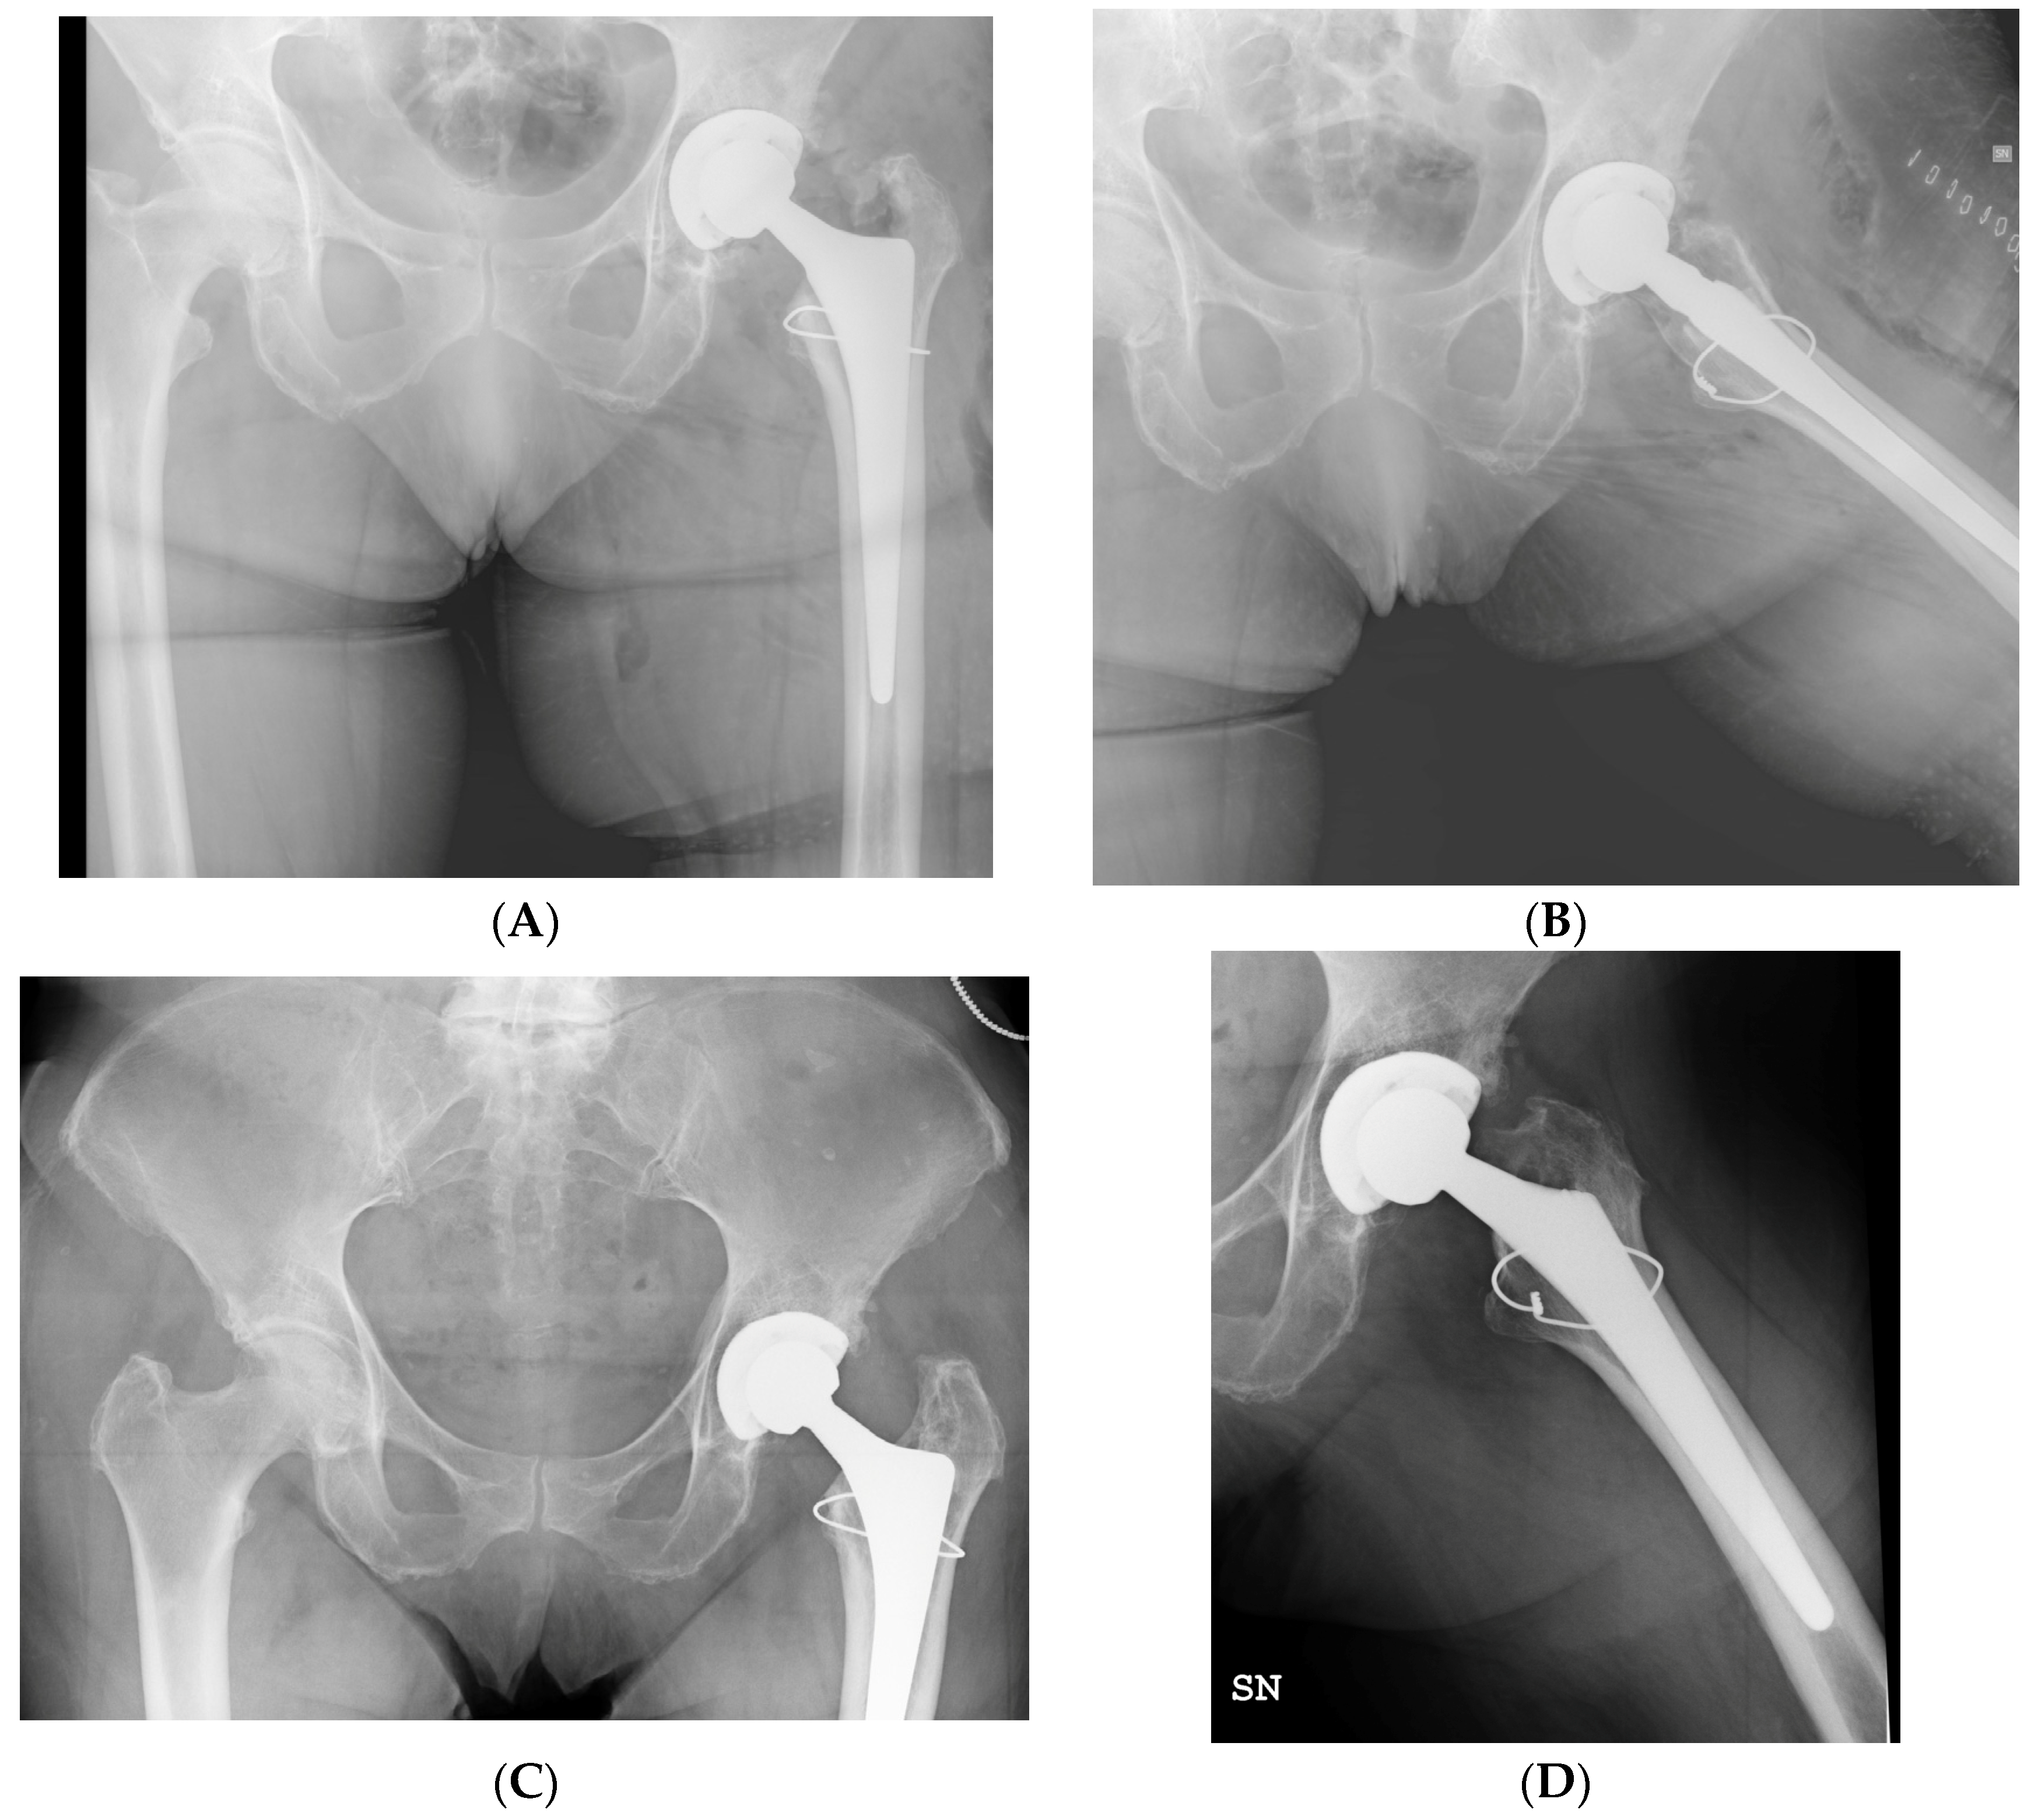

The mean HHS and LLD were subject to significant postoperative improvement, as reported in Table 7. Radiographic examples of a successful treatment and a failure model are displayed in Figure 2 and Figure 3.

Figure 2. (A,B) Postoperative radiographs show the VB1 fracture of a 68-year-old female, treated with single metal cerclage cabling during primary total hip arthroplasty. (C,D) Subsequent radiographic assessments at 19 months follow-up demonstrate excellent healing of the fracture, with no indications of periosteal reaction or mobilization of the stem.